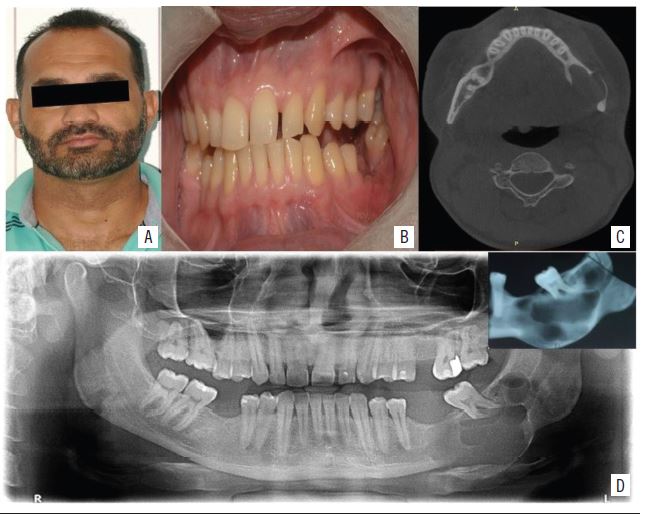

A 36-year-old mixed-race male patient searched for the service of Oral Maxillofacial Surgery and Traumatology of Universidade Federal do Rio Grande do Norte (UFRN) complaining of pain during masticatory movements in the posterior region of the left mandible. Clinical examination showed accentuated mobility of the second lower left molar and slight volume increase in left mandible region, with no intraoral volumetric changes (Figure 1 A and B). The panoramic imaging examination also considered multilocular radiolucent osteolytic lesion, with cortical basilar expansion, root resorption of the second left lower molar and involvement of body, angle and ramus of the left mandible (Figure 1C).

Given these findings, the following were ordered: multislice computed tomography (CT) for a more detailed evaluation of the lesion (Figure 1D), confection of a prototype biomodel for surgical planning, as well as laboratory tests and surgical risk evaluation for the conduction of lesion resection and immediate reconstruction.